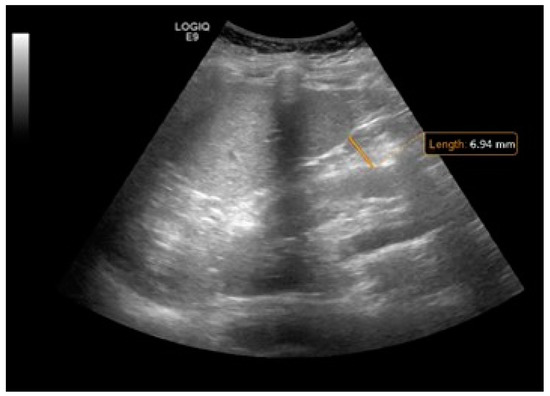

- De Lucia Rolfe, E.; Modi, N.; Uthaya, S.; Hughes, I.A.; Dunger, D.B.; Acerini, C.; Stolk, R.P.; Ong, K.K. Ultrasound estimates of visceral and subcutaneous-abdominal adipose tissues in infancy. J. Obes. 2013, 2013, 951954. [Google Scholar] [CrossRef] [PubMed]

- Wagner, D.R. Ultrasound as a tool to assess body fat. J. Obes. 2013, 2013, 280713. [Google Scholar] [CrossRef] [PubMed]

- Liem, E.; Rolfe, E.D.L.; L’abee, C.; Sauer, P.; Ong, K.; Stolk, R. Measuring abdominal adiposity in 6 to 7-year-old children. Eur. J. Clin. Nutr. 2009, 63, 835–841. [Google Scholar] [CrossRef]

- Koot, B.; Westerhout, R.; Bohte, A.; Vinke, S.; Pels Rijcken, T.; Nederveen, A.; Caan, M.; Baan-Slootweg, O.; Merkus, M.; Stoker, J. Ultrasonography is not more reliable than anthropometry for assessing visceral fat in obese children. Pediatr. Obes 2013, 9, 443–447. [Google Scholar] [CrossRef] [PubMed]

- Mook-Kanamori, D.O.; Holzhauer, S.; Hollestein, L.M.; Durmus, B.; Manniesing, R.; Koek, M.; Boehm, G.; Van der Beek, E.M.; Hofman, A.; Witteman, J.C. Abdominal fat in children measured by ultrasound and computed tomography. Ultrasound Med. Biol. 2009, 35, 1938–1946. [Google Scholar] [CrossRef] [PubMed]